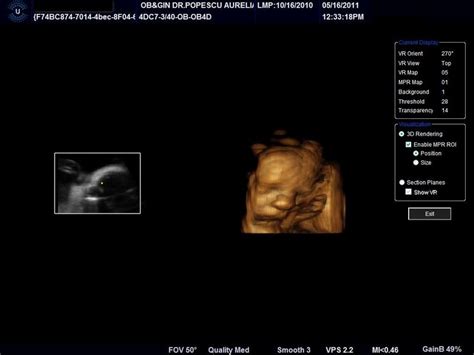

Morfologia fetală realizată în cel de-al doilea trimestru de sarcină permite observarea în timp real a mișcărilor, iar medicul poate realiza reconstrucții 3D și 4D ale fătului. Mai mult, se pot vedea cordonul ombilical și placenta, astfel încât posibilele complicații să fie descoperite din timp.

Acest examen morfologic se realizează cu ajutorul unui ecograf de ultimă generație, ce funcționează cu ajutorul ultrasunetelor. Echipamentul este dotat cu un soft de obstetrică și ginecologie și prezintă un ecran pe care apar imagini 3D sau 4D în timp real. Sunt efectuate o serie de măsurători a diferiți parametri morfologici ai fătului, precum și o evaluare amănunțită a placentei, lichidului amniotic, uterului etc.

Morfologia fetală realizată în cel de-al doilea trimestru de sarcină permite observarea în timp real a mișcărilor, iar medicul poate realiza reconstrucții 3D/4D ale fătului. Mai mult, este posibilă vizualizarea cordonului umbilical și a placentei, astfel încât eventualele complicații să fie descoperite din timp.